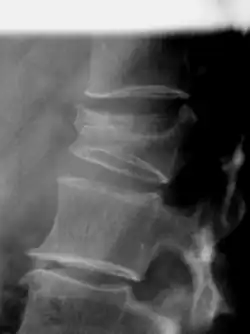

Der Eingriff wird typischerweise in Bauchlage unter Röntgendurchleuchtung durchgeführt. Eine Durchführung in Lokalanästhesie ist möglich, häufiger wird die Operation in Narkose durchgeführt. Dabei schläft der Patient auf dem Bauch liegend, der Rücken wird desinfiziert und mit sterilen Tüchern abgedeckt. Unter Röntgenkontrolle werden abhängig von der Technik ein oder zwei Kanülen über die Wirbelbögen in den Wirbelkörper eingebracht und anschließend das Wirbelkörperinnere für die Materialimplantation (meist Knochenzement auf PMMA-Basis) vorbereitet. Im herkömmlichen Verfahren werden dabei ein oder zwei Ballone eingeführt, mit Kontrastmittel aufgefüllt und dadurch die umliegende Spongiosa zerquetscht. Der dabei entstehende großvolumige Hohlraum wird mit normalem Knochenzement aufgefüllt. Dauer: ca. 45 Min.